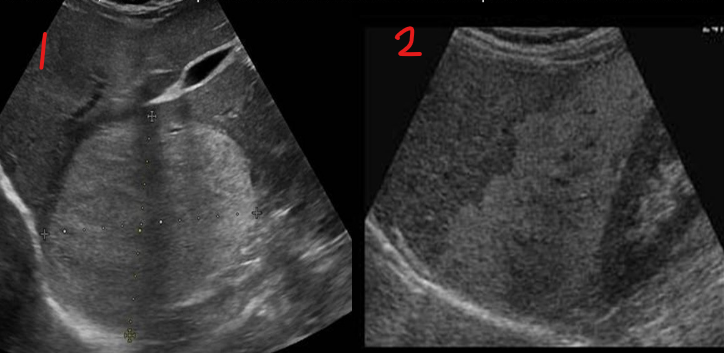

Identify this image.

Mild fatty liver

Severe fatty liver